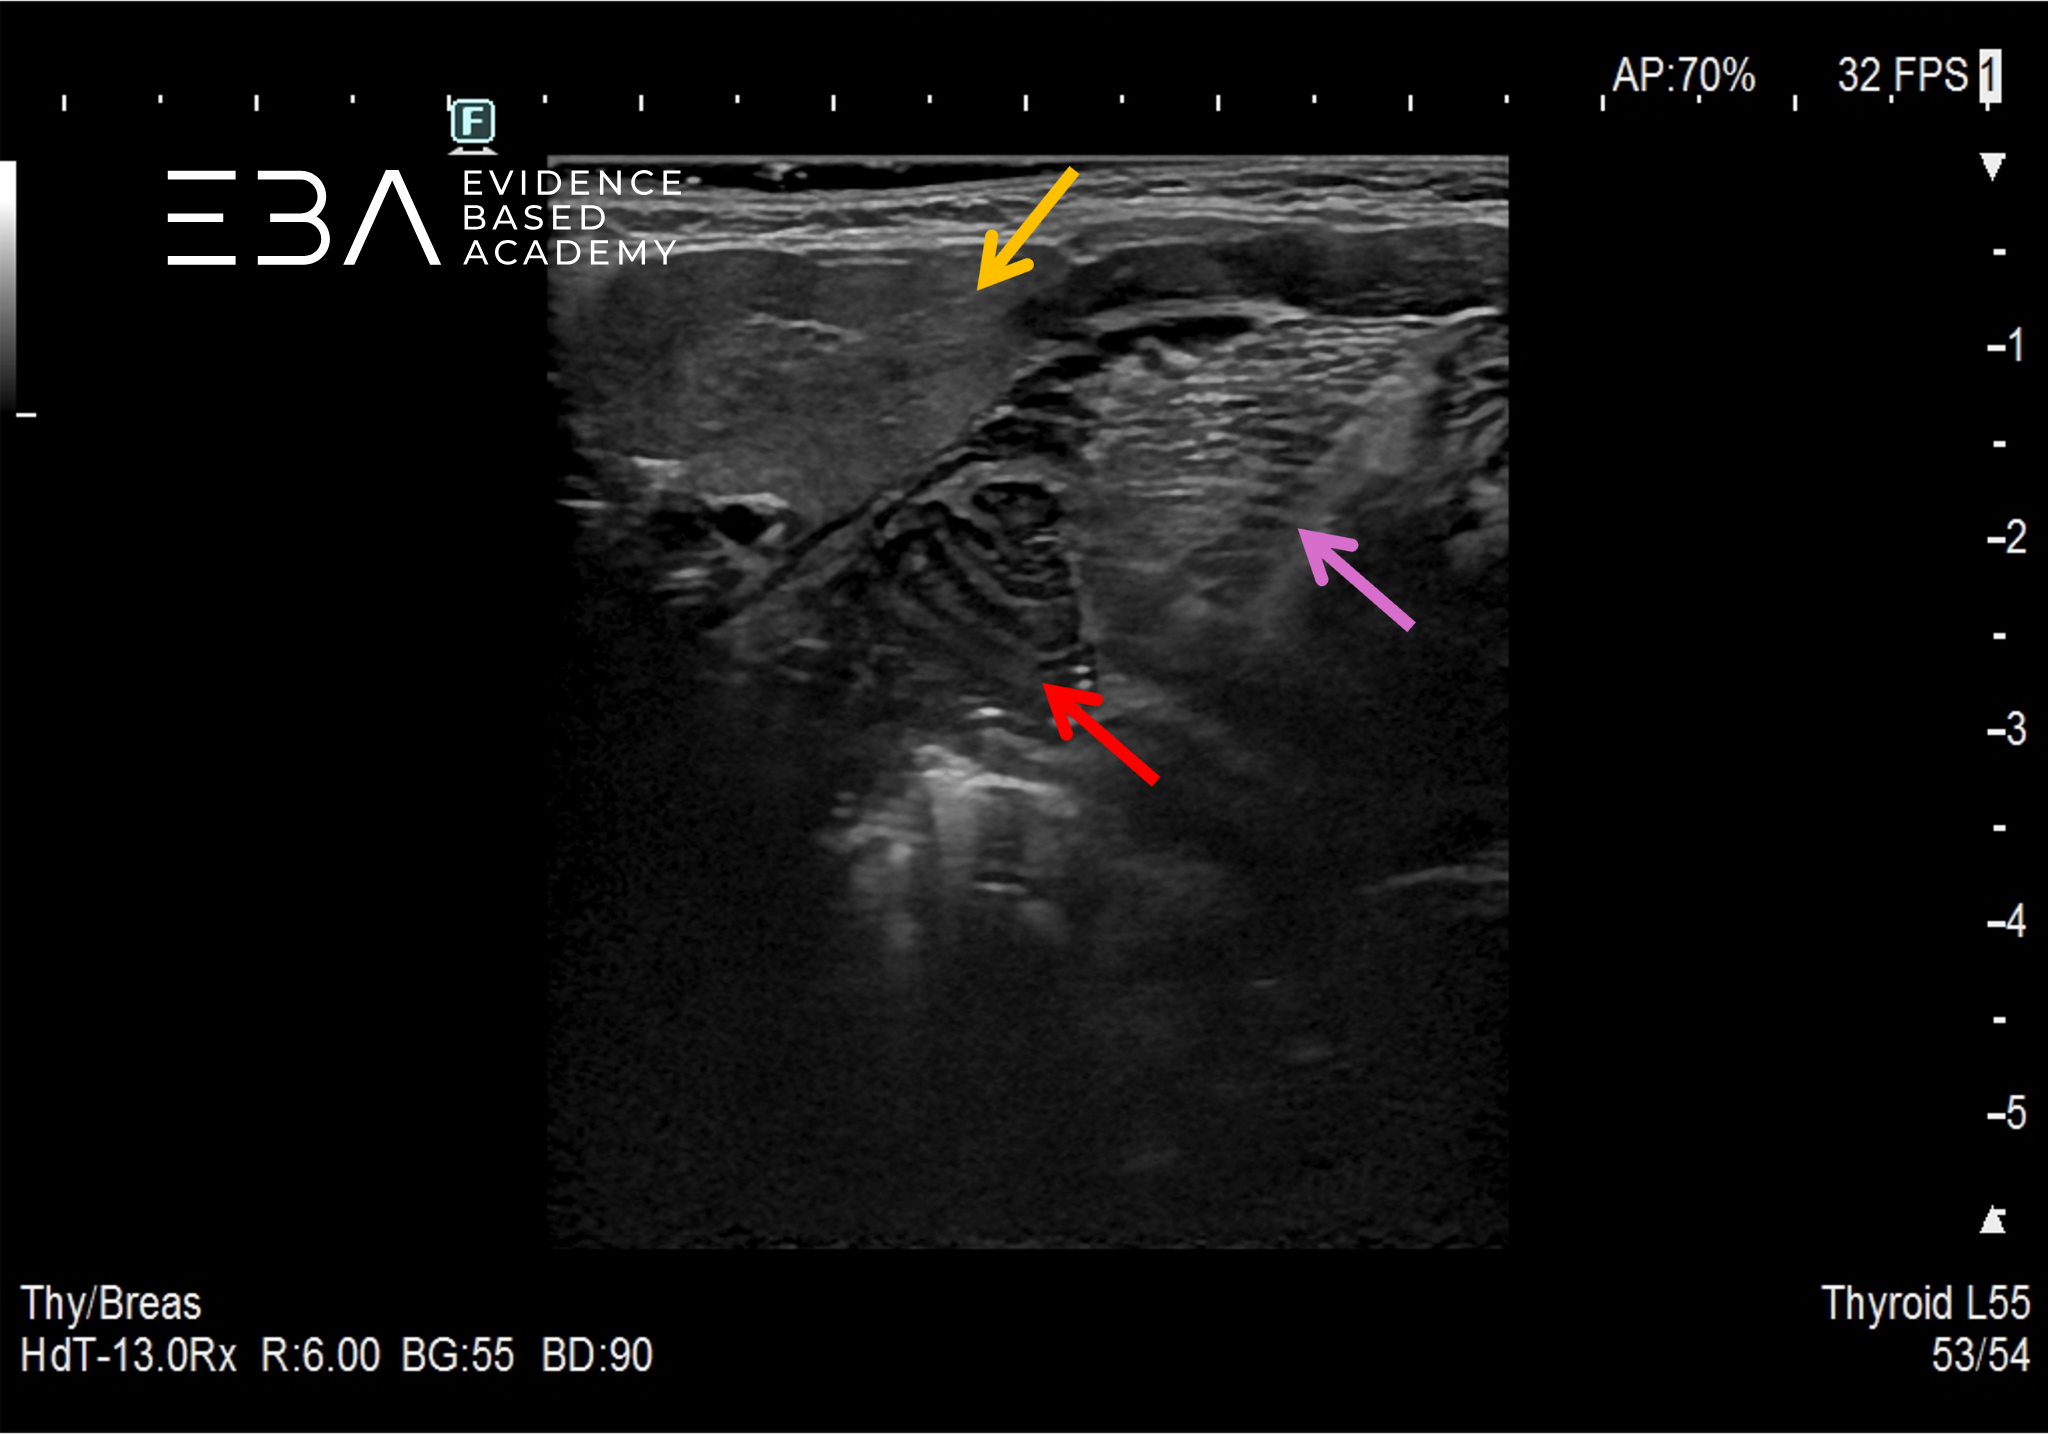

9. Ślinianka podżuchwowa (pomarańczowa strzałka) w projekcji podżuchwowej. Czerwoną strzałką oznaczono migdałek podniebienne z widocznymi kryptami. Fioletową strzałką oznaczono język.